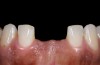

Fig. 2  Preparations for laminate veneers.

Figure 2

The clinical application of this protocol is illustrated in a patient situation where laminate veneers were placed on four maxillary incisors to replace lost tooth structure and restore function and esthetics. The failing restorations were removed, followed by a conservative veneer preparation (Figure 1 and Figure 2). The bonding surfaces of the feldspathic porcelain veneers were acid-etched with hydrofluoric acid for 2 minutes (Figure 3) and thoroughly rinsed. Then a silane coupling agent was applied (Figure 4). Figure 5 demonstrates the situation after bonding the veneers to the teeth with a composite resin luting agent.